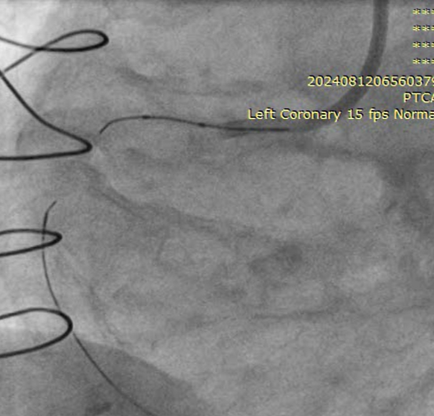

LMCA: distal mild stenosisLAD: diffusely disease from proximal part with total occlusion in mid part with competitive fillingD1, Ramus, OM1- total occlusionLCX: mild diffuse disease RCA: CTO from proximal part, retrograde filling from LADLIMA to LAD: patentSequential LIMA - RIMA “Y” to OM1 to PDA: occludedSequential RSVG to ramus to PLV branch of RCA- occluded

RSVG to Ramus to PLV was engaged with 7F AR-1 guide catheter. Occluded segment in RSVG crossed with Pilot-150 PTCA wire with Caravel micro-catheter and parked into distal RCA. Position of the wire and micro-catheter confirmed with retrograde injection from native LMCA. Retrograde wiring was attempted with Gaia NexT-2, Pilot-150, Pilot-200 PTCA guide wires, but was unsuccessful. Native RCA was engaged with 7F AL 0.75 guide catheter and antegrade wiring was attempted with micro-catheter support and Gaia NexT-2, Pilot-150 followed by Pilot-200 PTCA guide wires, but was unsuccessful. Balloon dilatation was done in proximal RCA with 2.0 x 10 mm SC balloon. Knuckle wire technique was used to cross the lesion from antegrade site but unsuccessful. Finally, lesion crossed with Asahi Gladius MG-14 wire from antegrade approach and wire parked into the RSVG. Micro-catheter exchanged. Serial predilatation was done with 0.75 x 8 mm SC balloon followed by 2.0 x 20 mm SC balloon. IVUS run was taken for vessel size estimation. 3.0 x 48mm DES was deployed from proximal RCA. Post dilatation was done with NC 3.5 x 8 mm balloon. Distal RCA was addressed with 2.75 x 30 mm DEB. Mid RCA was stented with DES 3.00 x 32 mm. Post-dilated with 3.0 x 10 mm NC balloon followed by 3.75 x 8 mm NC balloon. Post-stenting IVUS run showed good stent expansion and apposition. Distal TIMI-III flow was achieved.